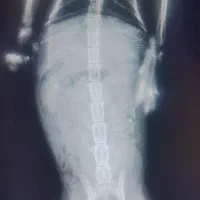

سلام من یه گربه تصادفی پیدا کردم ۱ هفته هم نگهداریش میکنم دکتر هم بردم عکس هم گرفتن جزعی کمرش زربه خورده دکتر گفته خوب میشه از کسی که شرایط نگهاریشو داره خواهشن تماس بگیره ممنون چون من صبح میرم سر کار شب میام نمیتونم کامل بهش برسم